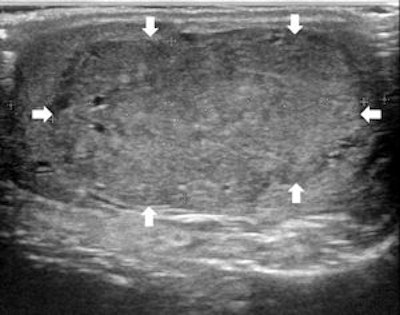

Top left: Grayscale ultrasound image of the testes showing a large isoechoic nodule (40 x 20 mm) compared with the testicular tissue (arrows). Top right: Color Doppler showing peripheral and central vascularization of the nodule, suggesting a malignant lesion. Bottom left: RTE of the nodule showing a large central strain area (mainly an intermediate elastic pattern displayed in green) (*) surrounded by a no-strain rim (the peripheral part of the lesion is blue) (arrows). This pattern, that the researchers suggested calling "score 3-inverted" (the opposite of the known color-coded score 3 reference of Itoh et al) seems to be related to the Leydig tumors. Bottom right: Gross specimen of the testicle. Histological diagnosis of the nodule was Leydig tumor, consisting of cells with abundant cytoplasm without interstitial fibrous stroma; the slow growth of the tumor induces sclerohyalinosis at the periphery. The tumor's macrostructure explains the RTE pattern.Because clinical examination has its drawbacks, ultrasound has become the imaging technique of choice for evaluating scrotal abnormalities -- with the primary function of ultrasound being the diagnosis of a testicular mass to distinguish intratesticular from extratesticular location. Most extratesticular masses are benign, but intratesticular ones are malignant.

In RTE evaluation, normal testicles mainly show a medium level of elasticity (displayed in green); some linear "red" structures within the testes are related to fluid component. Sometimes the glandular tissue below the tunica albuginea of the testicle presents less relative strain, displayed in light blue, probably due to the limited tissue displacement determined by the fibrous covering, the researchers wrote.